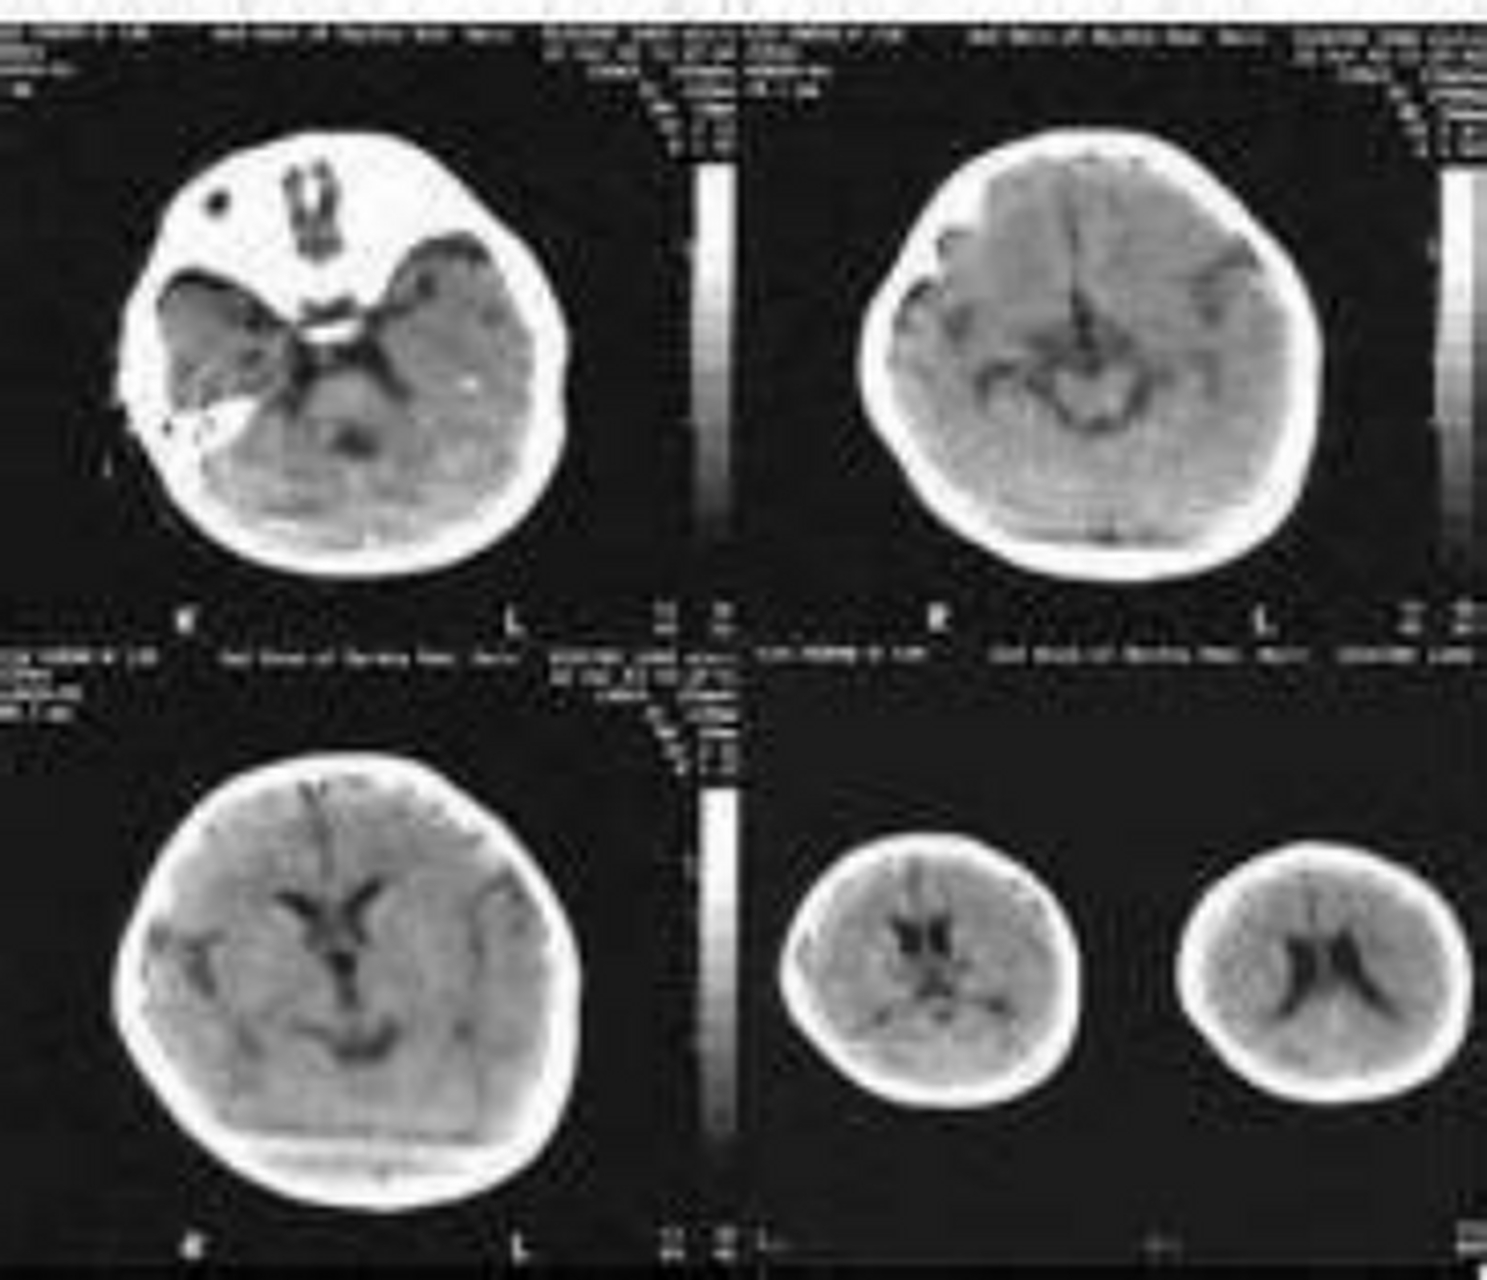

乙型脑炎是由乙脑病毒引起的急性中枢神经系统传染病,经蚊虫媒介传播流发于夏秋季节,具有典型的季节性,尤以儿童多见临床特征为高热意识障碍惊厥脑膜刺激征脑症状等,重者引起呼吸衰竭人对乙脑普遍易感感染后可获持久的免疫力各年龄段均可发病,主要在10岁以下,尤以2~6岁儿童发病率。

流行性乙型脑炎属于中华人民共和国传染病防治法中规定的乙类传染病,是由乙脑病毒引起经蚊传播的人畜共患的中枢神经系统急性传染病潜伏期一般在1014天左右患者主要表现发烧剧烈头痛恶心呕吐嗜睡不醒等症状,重者可出现抽搐昏迷,甚至出现呼吸衰竭而死亡传染源是被感染的人或动物。